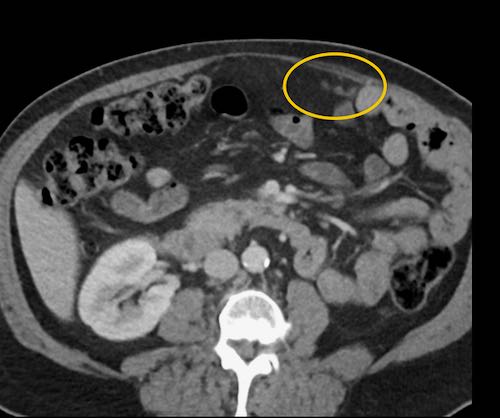

Cuộn xem ảnh CT

Ca lâm sàng 1

Cuộn qua các lát cắt.

Bạn có thể phát hiện tất cả các tổn thương cấy ghép phúc mạc không?

Bệnh nhân này đã được phẫu thuật và toàn bộ phúc mạc được ghi nhận phủ kín bởi các tổn thương u dạng kê.